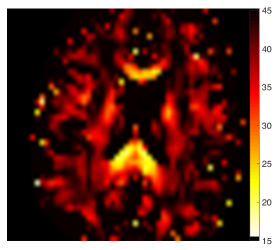

Branch selection. Out of the two parameter branches, only one corresponds to the biophysical reality, and the other should be discarded. Branch selection is nontrivial, Sec. 4.4, as it depends on the ground truth values, and is generally brain region-specific, as we show in Figs. 3-5 based on 21-shell human dMRI with .

In Figures 3 and 4 we demonstrate the double degeneracy of parameter estimation problem (1)–(2), anticipated from topology of Fig. 2, using a dedicated human dMRI acquisition (cf. Methods). We first solve the LEMONADE system (11) (using subset with ), map all parameters (cf. Fig. 3 lemo ), and plot histograms for its both branches (red and blue dotted lines in Fig. 4) in white matter (WM, voxels), and in gray matter (GM, voxels), selected using probability masks. (WM mask was further thresholded by to minimize partial volume effects.)

We then use pairs of LEMONADE solutions with in each voxel to initialize the full gradient-descent nonlinear RotInv minimization (7), for which all the data with is used (cf. Fig. 3 RotInv ). This leads to the corresponding shaded histograms in Fig. 4. We can see that the output of full optimization (7) is qualitatively similar to that based on the Taylor expansion (8), with bimodal parameter histograms corresponding to the fundamental degeneracy of the parameter landscape corresponding to the two distinct branches of solutions.

Our analysis shows that the two branches are qualitatively distinct in the following ways: ; also, usually, for and for (cf. Eq. (13) below). Generally, neither solution can be discarded based on parameter values alone, as they often fall within plausible biophysical bounds and . (We show values up to to illustrate the role of noise in broadening the histograms.) Figure S.4 in Supplementary Section S.3 shows that improvement in accuracy gained by nonlinear minimization (7) relative to LEMONADE occurs because small errors in estimated moments in the finite range of translate into greater errors in the LEMONADE solutions, mostly due to errors in estimating the moment tensor .